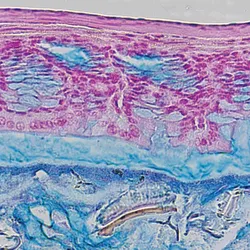

Antibiotics disrupt the beneficial mucus barrier lining the gut

Antibiotics target bacteria, but new work in mice shows they also harm the mucus layer that protects the intestinal lining from microbes.Editor's Insight